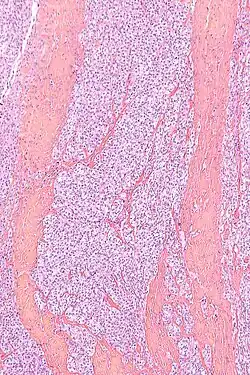

W obrazie mikroskopowym utkanie guza tworzą gęste gniazda lub pęczki komórek wrzecionowatych lub poligonalnych pooddzielane przegrodami łącznotkankowymi. Komórki o wrzecionowatym lub wielobocznym kształcie są wyraźnie odgraniczone, posiadają obfitą jasną lub słabo eozynofilną cytoplazmę z pęcherzykowym jądrem i wydatnym bazofilnym jąderkiem[2][9]. Aktywność mitotyczna jest niska, podobnie stopień pleomorfizmu jest niewielki. W około połowie guzów obecne są wielojądrowe komórki olbrzymie oraz ogniska melaniny[2].